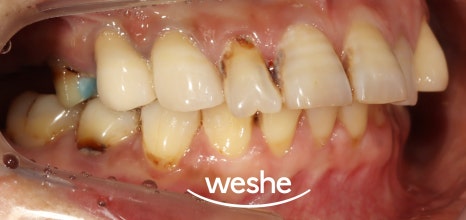

먼저, 엑스레이와 구강 내 모습을 보며

검진을 진행합니다.

예시 사진에서는

치주 질환과 충치로 인해 잇몸뼈가 내려앉거나

치아머리가 사라져 있는 것을

확인할 수 있습니다.

이러한 문제는

자연치의 기능을 하지 못하기에

발치 후 임플란트 를 하는 것이

하나의 방법입니다.